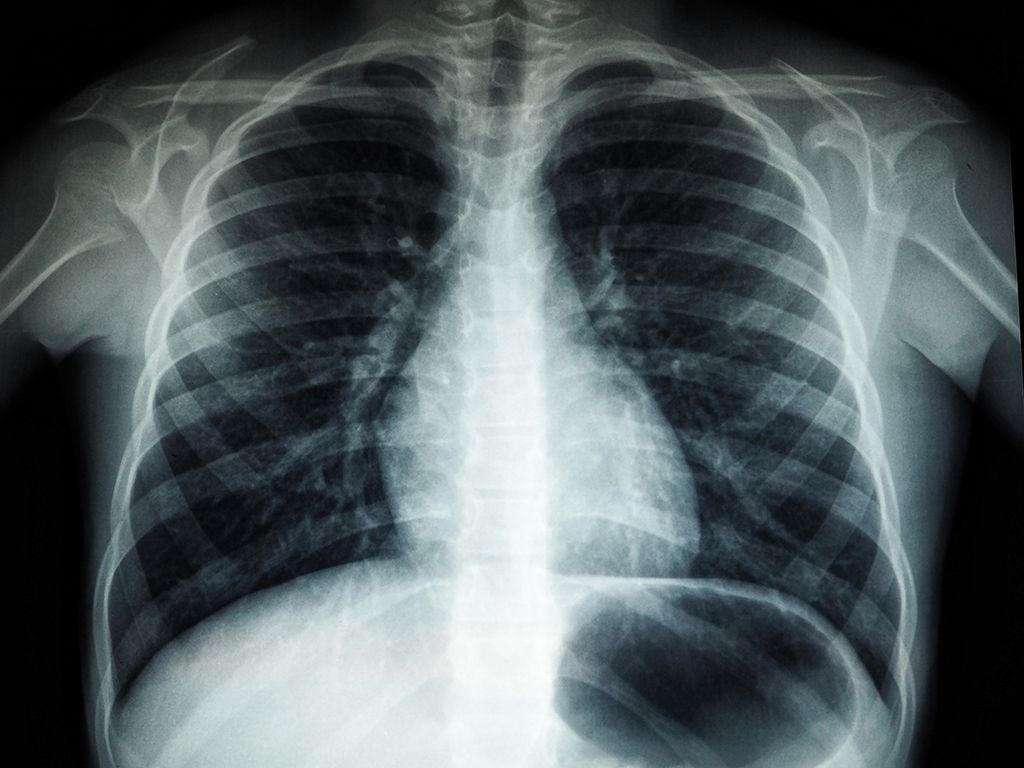

My father went to the hospital with chest pains, and they decided to do an angiogram. The process injects dye into his valves to look for clots.

During his procedure, the surgeon asks if he suffers from blackouts, and a few more doctors get called in to have a look. My dad is the strong silent type but admits to minimal daily pain.

They take him to another type of X-ray machine and again are looking in bemusement without explaining anything. Turns out there was a blood clot the size of a golf ball floating free in his heart.

It normally should have taken out someone quickly and the doctors were all intrigued. He had a triple bypass 30 years ago and is still the strong and silent type. Story credit: Reddit / monkeypowah